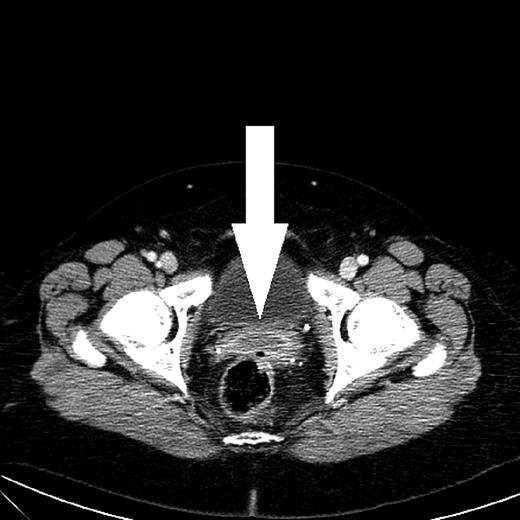

A control CT scan 3 months after the initial admission showed complete regression of the pelvic abscess. Furthermore, a 2 × 3 cm abdominal wall abscess was found behind the superior part of the right rectus abdominis muscle, equivalent to the port site where the perforated gall bladder was extracted 17 years earlier (Fig. 2). Ultrasonically guided biopsy showed acute inflammation and Escherichia coli.

CT scan shows an abscess with peripheral rim enhancement beneath the right rectus abdominis muscle. A simple cyst of the right kidney was a coincidental finding.